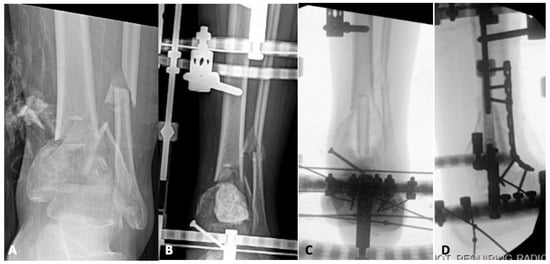

Radiological Landmarks for Joint Line Level in Challenging Total Ankle Arthroplasty

Background: Although Total Ankle Arthroplasty (TAA) is primarily performed for post-traumatic ankle arthritis with joint disruption, anatomical landmarks for Joint Line (JL) level are typically preserved. However, severe Post-Traumatic Bone Loss (PTBL) or TAA revision may render some landmarks unidentifiable, challenging JL restoration. [...] Read more.

Background: Although Total Ankle Arthroplasty (TAA) is primarily performed for post-traumatic ankle arthritis with joint disruption, anatomical landmarks for Joint Line (JL) level are typically preserved. However, severe Post-Traumatic Bone Loss (PTBL) or TAA revision may render some landmarks unidentifiable, challenging JL restoration. Methods: Patients undergoing customized TAA for severe PTBL or revision were enrolled. Custom-made implants, based on 3D CT scans, were designed to address bone defects and provide adequate bone support. Evaluated parameters, measured on bilateral ankle weight-bearing radiographs taken preoperatively and 6–8 months postoperatively, included JL Height Ratio (JLHR) and the distances from JL to the Lateral Malleolus apex (LM-JL), the posterior colliculus of the Medial Malleolus (MM-JL), and the Gissane Calcaneal Sulcus (CS-JL). Reproducibility and variability were assessed, and comparisons were made between radiological parameters measured at TAA and those at the contralateral ankle. Results: Thirteen patients were included. Intra- and interobserver reliability demonstrated excellent values. The least variability was observed in the LM-JL distance. Statistically significant correlations were found between CS-JL and MM-JL distances in the operated limb and between the CS-JL of the operated limb and the contralateral ankle. While TAA parameters did not show statistically significant differences compared with the contralateral ankle, a trend toward proximalization of the JL was noted. Conclusions: This study demonstrated good reproducibility of the analyzed parameters for evaluating JL in TAA among patients with severe PTBL or undergoing revision surgery. However, these parameters cannot be deemed fully reliable. Given their potential weaknesses, it is crucial to identify more reproducible values, preferably ratios. Full article

Figure 1